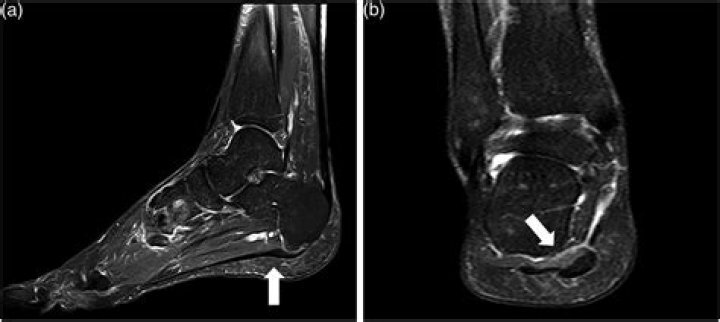

Even though there is no significant difference between the accuracy of ultrasound and MRI regarding the measurements of the PF thickness [73], MRI is cons...